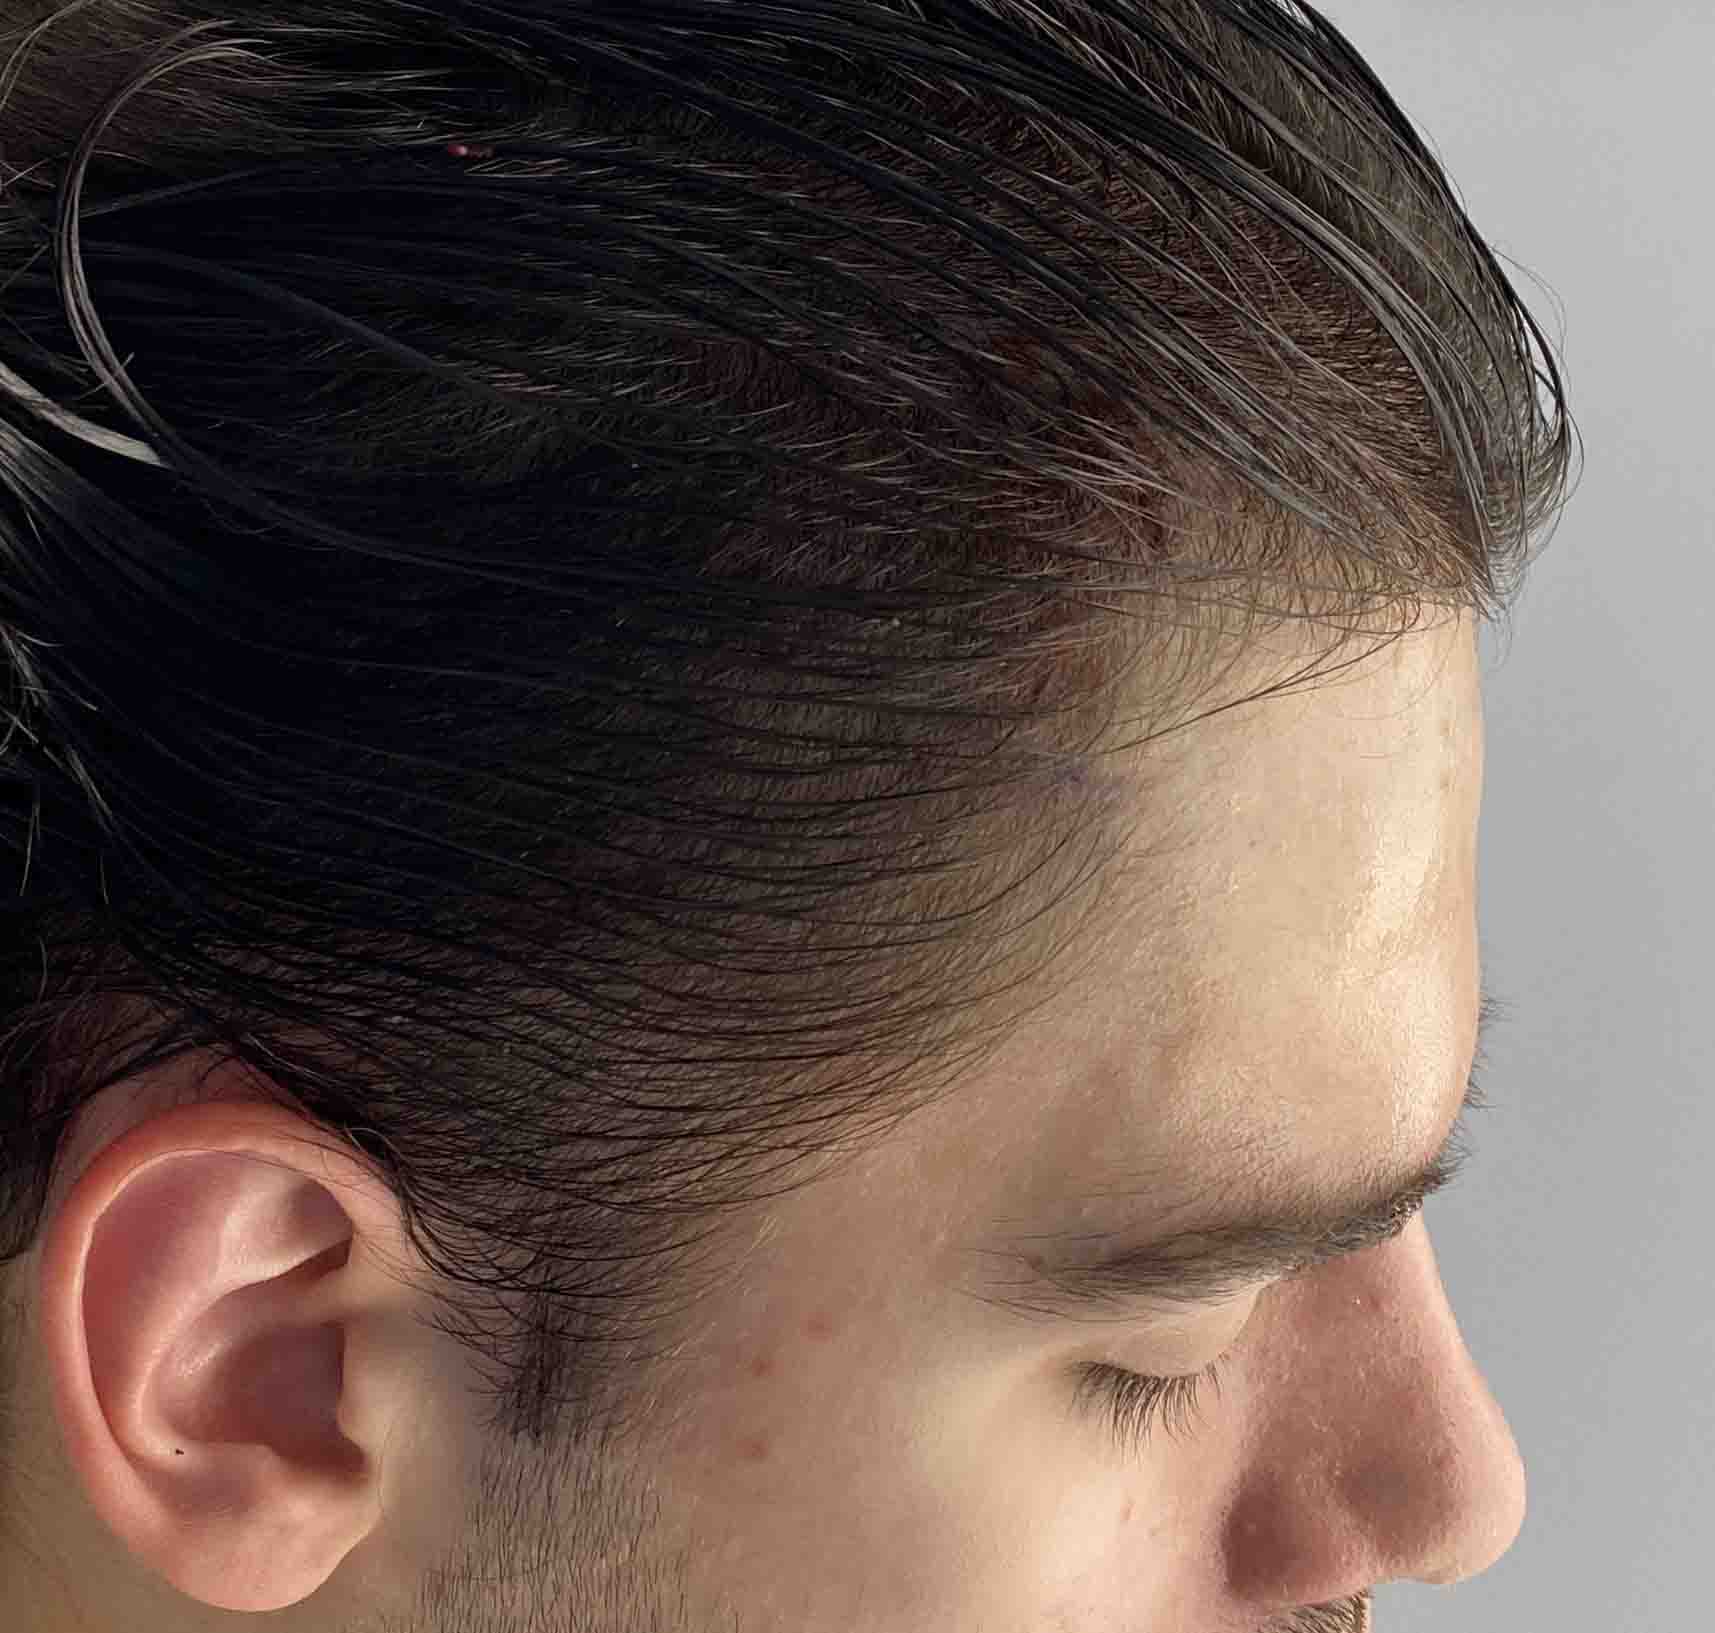

Patient 49

Desire for further skull augmentation after a primary skull implant.

Five years after an initial custom skull implant placement a new custom skull implant that increased the volume by 35% was placed.

Desire for further skull augmentation after a primary skull implant.

Five years after an initial custom skull implant placement a new custom skull implant that increased the volume by 35% was placed.